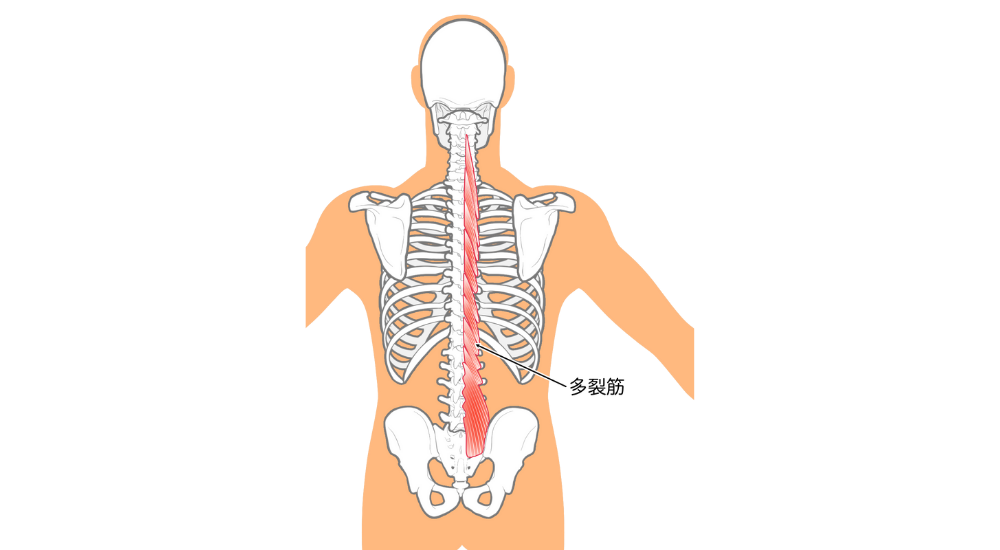

- 背骨周りの筋肉と深層筋(脊柱起立筋、多裂筋など):

背骨の近くには自律神経幹が走行しており、これらの筋肉の緊張や背骨の歪みが自律神経に影響を与える可能性があります。

これらの筋肉の慢性的な緊張は、身体を常に「戦闘モード」に近い状態にさせ、自律神経のバランスを崩すことで、慢性的な疲労感や気分の落ち込みに繋がるのです。